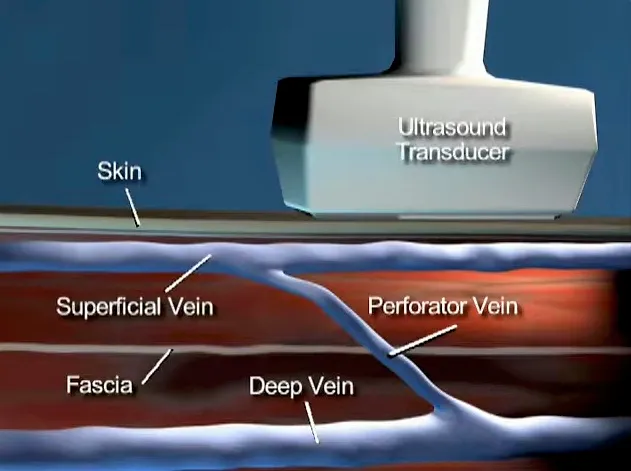

5. 穿支静脉反流 (PVR) 的治疗

许多医生忽略了作为静脉反流模式的一部分的IPV。1985年以前,除了开放结扎术外,没有其他治疗方法。然而,1985年Hauer发明了筋膜下内镜穿支静脉(subfascial endoscopic perforating vein, SEPS)手术,将内镜引入膝下筋膜下间隙,在筋膜下夹闭静脉。然而,SEPS仍需要2 ~ 3 cm的切口,通常需要全身麻醉,术后肌肉操作带来的不适较多,且穿支血管的处理局限在小腿内侧。2000年,发明了经腔穿支静脉闭塞 (TRansluminal Occlusion of Perforators, TRLOP) 手术。

在超声控制下,对IPV进行插管,并在穿支置入消融装置。最初使用射频,后来使用腔内激光。TRLOP在2007年被“重新定义“为“穿支消融术“ (PAPS),尽管两种技术之间没有任何差异。其他工作者通过注射氰基丙烯酸酯胶进一步改进了这一点。TRLOP方法可与这些方法中的任何一种一起用于IPV的局部消融,即使静脉较短。

超声引导下经腔穿支静脉闭塞 (TRansluminal Occlusion of Perforators, TRLOP) 手术。

一些医生主张用UGFS关闭IPV。由于UGFS流经局部静脉,而不会停留在注射部位,因此对IPV进行的UGFS治疗可能导致穿支血管消融不足(泡沫过少),或增加治疗区域局部静脉发生深静脉血栓 (DVT) 的风险(泡沫过多)。因此,尽管已经描述了这一点,但对IPV进行UGFS治疗时,应了解这样做的风险,并且在不可能做TRLOP的情况下进行。